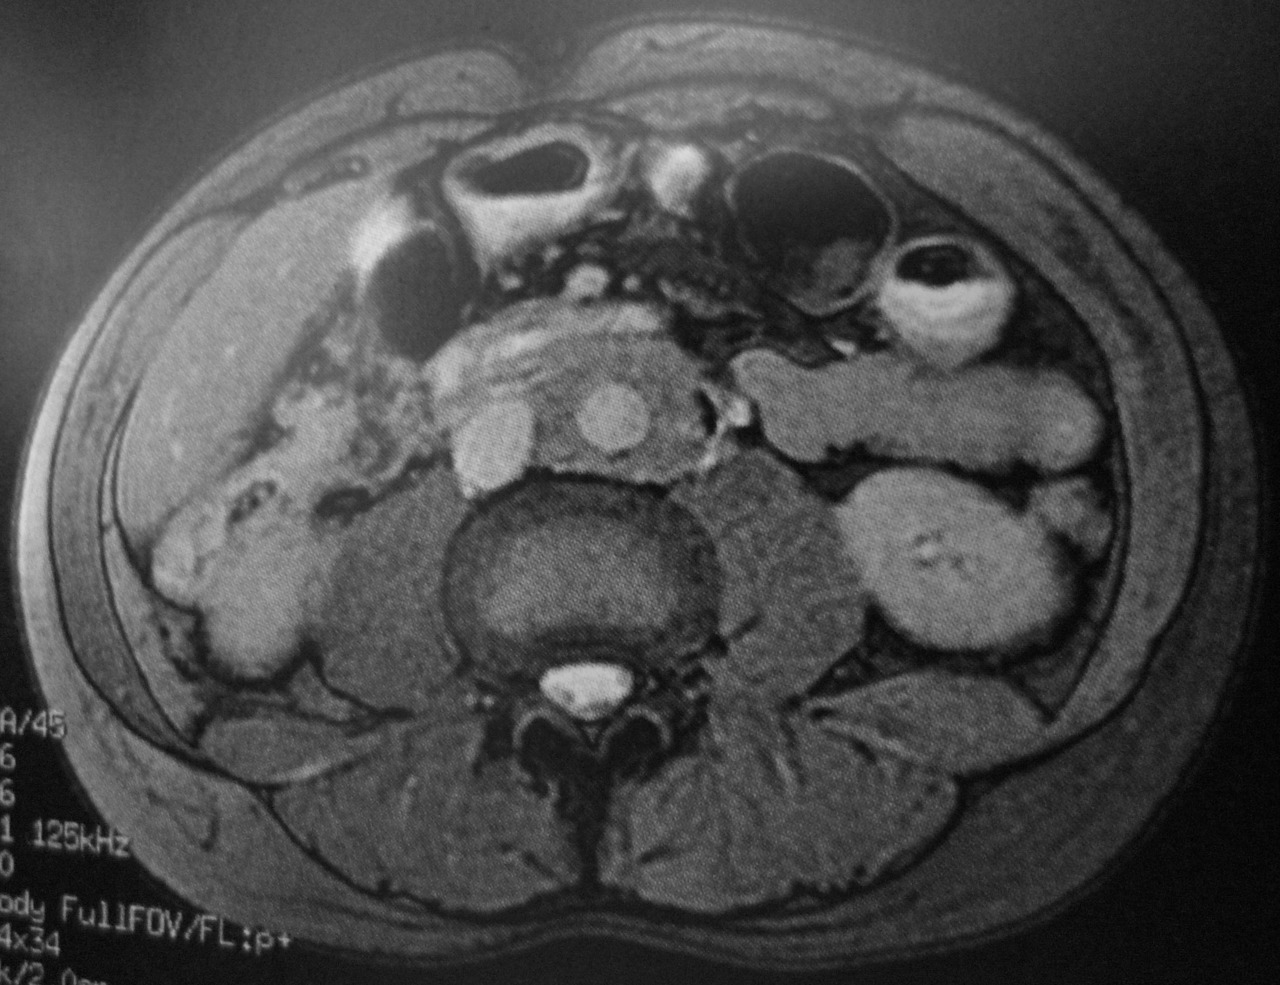

Quel est votre diagnostic? Maladie d'Erdheim-Chester Lymphome Fibrose rétropéritonéale Léiomyosarcome Anevrisme aorte abdominale OK Il s'agit de la fibrose rétropéritonéale. Valider mes réponses

Il s'agit de la fibrose rétropéritonéale.